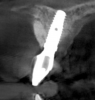

After 3 months of post-orthodontic stabilization, a cone-beam computed tomography scan was taken to re-evaluate the results and plan the future treatment sequence. Tomographic images clearly showed vertical gains in alveolar height, including in the edentulous area corresponding to tooth No. 7 (Figure 10 through Figure 12). The apex of tooth No. 8 was forced-erupted beyond its socket and could be visibly located within the soft tissue.30,33

Fig 10. Tomographic images of teeth Nos. 6 (Fig 10), 7 (Fig 11), and 8 (Fig 12) clearly showed vertical gains in alveolar height, including in the edentulous area corresponding to tooth No. 7. The apex of tooth No. 8 was located within the soft tissue because it was force-erupted beyond its socket.

Figure 10

Fig 11. Tomographic images of teeth Nos. 6 (Fig 10), 7 (Fig 11), and 8 (Fig 12) clearly showed vertical gains in alveolar height, including in the edentulous area corresponding to tooth No. 7. The apex of tooth No. 8 was located within the soft tissue because it was force-erupted beyond its socket.

Figure 11

Fig 12. Tomographic images of teeth Nos. 6 (Fig 10), 7 (Fig 11), and 8 (Fig 12) clearly showed vertical gains in alveolar height, including in the edentulous area corresponding to tooth No. 7. The apex of tooth No. 8 was located within the soft tissue because it was force-erupted beyond its socket.

Figure 12